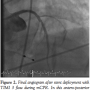

Case 4. A 75-year-old woman with a past history of hypertension and diabetes presented with 3 hours of unrelenting chest pain with associated hypotension. After pre-hospital ECG confirmed inferior STEMI, she was brought to our facility by EMS for primary PCI. While awaiting transfer to the CCL, she experienced her first PEA cardiac arrest with successful return of spontaneous circulation (ROSC) after CPR, epinephrine, and atropine. She experienced recurrent PEA arrest immediately prior to and during angiography and PCI. The patient received

manual CPR and was intubated. Coronary angiography demonstrated a thrombotic culprit mid RCA occlusion (Figure 7). PTCA was performed during continuous mCPR (Figure 8) with subsequent ROSC. A bare-metal stent was placed in the mid RCA with restoration of TIMI 3 flow. An IABP was placed following left coronary angiography and the patient was transferred to the CCU on vasopressors. Despite increasing pressor support, the patient expired 12 hours later with a progressive sepsis-like syndrome.

Fluoroscopic and cineangiographic imaging during mCPR with the LUCAS device requires few significant adjustments. The images presented here represent one center’s experience and diagnostic images were obtained in all cases. Anterior-posterior projections are limited by the height and radio-opacity of the LUCAS drive unit over the patient’s chest. Straight right and left anterior oblique views provide adequate visualization despite the back-brace component of the device being visible on fluoroscopy. As evidenced in Cases 1 and 4, significant cranial angulation (>30°) can provide coronary imaging without visual encroachment by the device components.

In animal models, cerebral blood flow during CPR is improved with mCPR,15 and mCPR devices provide significantly higher coronary perfusion pressures than manual CPR.16 Coronary flow assessment has been reported in both animal models and human subjects.16,17 In 4 out of 6 patients studied by Larsen et al with TIMI 3 flow during mCPR, invasive measurements documented adequate coronary perfusion pressure gradients. In the present experience, coronary flow during mCPR is pulsatile, but classification by TIMI grade is readily apparent. In Cases 1, 4, and 5, the PCI procedure itself was performed during mCPR compressions (Figures 1, 2, 8, and 10).